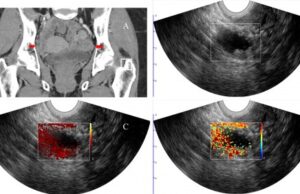

Photoacoustic ultrasound imaging shown to improve diagnostic accuracy of cancerous ovarian...

Published in the December 2023 issue of Ultrasound in Obstetrics and Gynaecology, Quing Zhu (Washington University, St Louis, USA) et al state that they...